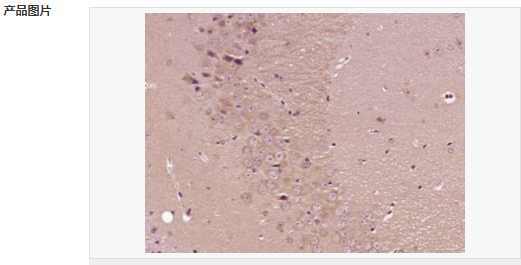

交叉反應(yīng):Mouse,Rat(predicted:Human,Pig) 推薦應(yīng)用:IHC-P,IHC-F,IF,ELISA

| 產(chǎn)品應(yīng)用 | ELISA=1:5000-10000 IHC-P=1:100-500 IHC-F=1:100-500 IF=1:100-500 (石蠟切片需做抗原修復) not yet tested in other applications. optimal dilutions/concentrations should be determined by the end user. |